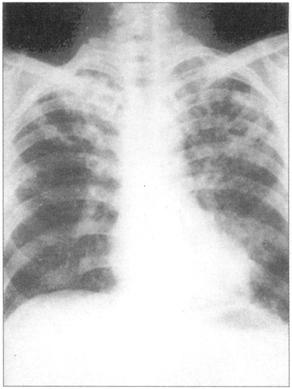

①周围性发绀及周围静脉扩张是由COPD引起的CO2潴留的主要特征(图76)。②脊柱侧后凸常预示患者有某种呼吸系统疾病的倾向(图77)。③结核的X线表现(图78)。④肺尖部结核所致的纤维化多引起上胸部变平(图79),由于脊柱常受累,故多有成角。⑤支气管肺癌(图80)。⑥大叶肺炎患者常伴发单纯疱疹病毒感染(图81、图82)。⑦如肺组织萎陷(如气胸),则胸片上无法看到肺纹理(图83)。

图83 右侧气胸伴肺纹理完全缺失